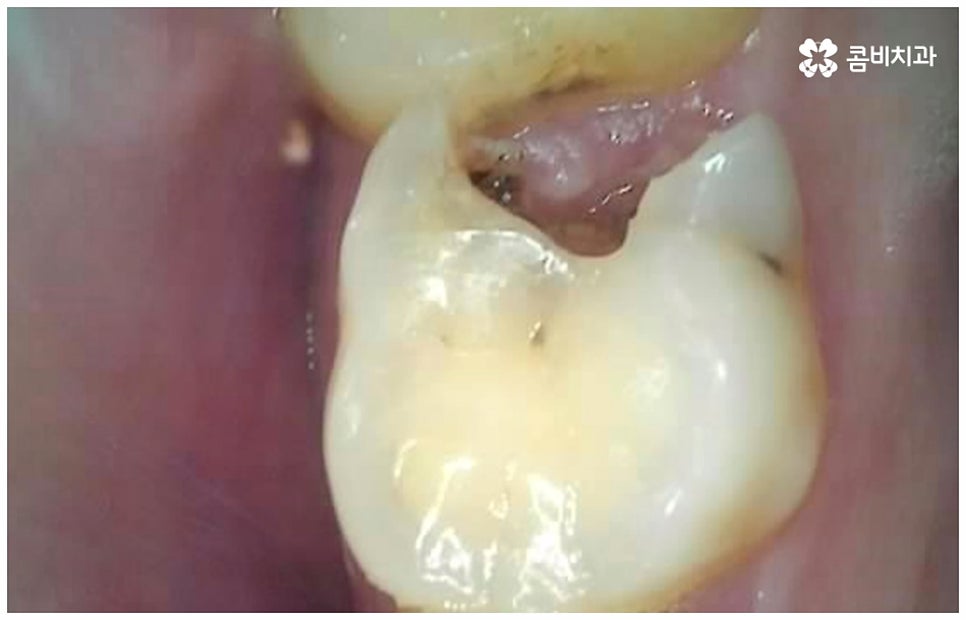

여기서 어금니신경치료 란 법랑질과 상아질을 지나 치아 안쪽 깊은 곳의 치수 조직까지 감염이 되었을 때 손상 부위를 모두 제거하고 치근관을 소독, 밀폐하는 치료를 의미하고 있는데요. 사람의 치신경은 아주 얇고 치근관의 모양과 개수는 모두 다 다른데 만약 끝이 구부러져 있거나 미세 부근관이 여러 갈래로 많이 퍼져 있는 경우, 신경관이 막힌 경우라면 신경을 제거할 때 난이도가 올라가므로 더욱 주의깊게 치료할 필요가 있어요.

감염 조직을 완전히 제거하지 않으면 통증이 지속될 수 있고 재발 가능성 또한 높아지므로 어금니신경치료 시 담당의 선생님의 높은 숙련도 및 세심한 기술력이 요구되고 있는데요. 혹시 모를 부작용을 방지하기 위해 3D CT 와 같은 정밀 진단 기계를 갖추고 신경관의 위치와 모양, 환자분들의 골조직 및 치아까지의 거리 등을 꼼꼼하게 파악하여 치료 계획을 세운 후 손상 부위를 세심하게 제거한다면 고난도의 경우라도 보다 안전하게 진행할 수 있어요.

어금니는 위치상 구강 내 가장 안쪽에 위치하므로 평상시 양치질을 잘 해 준다고 해도 음식물 찌꺼기가 남아있을 가능성이 커 충치 발생률이 높은 치아라고 할 수 있는데요. 이렇게 충치로 인한 손상 때문이 아닌 다른 이유로 어금니신경치료 를 진행해야 하는 경우도 있을 수 있어요. 예를 들어 20살 전후로 사랑니가 나오면서 삐뚤어지거나 일부가 매복된 채로 비정상적인 맹출을 하게 되면 앞의 어금니 뿌리에 압박을 주는 등 좋지 않은 영향을 줄 수 있는데요. 이 때 바로 사랑니를 발치하지 않고 그대로 방치한 채 시간이 오래 흘러 어금니까지 손상이 생겼을 경우 어금니신경치료 를 받아야 할 수 있어요. 그밖에도 외부에서 큰 충격을 받아 어금니가 깨지거나 부러져서 드물게 신경이 노출된 경우에도 감염된 신경 제거가 필요할 수 있는데요.